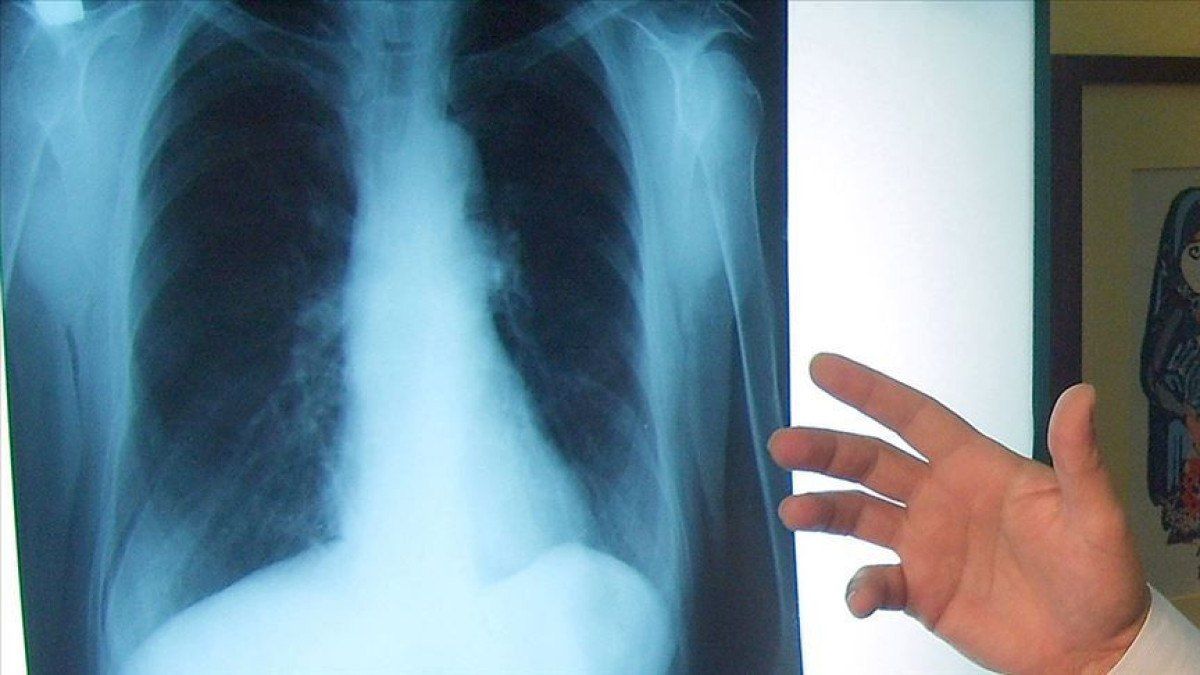

Sigara içen bireylerde akciğer kanseri görülme riski, diğer bireylere göre 30 kata varan bir oranda fazla. Her 4 akciğer kanserinin 3’ü sigara ile ilişkili. Erken tanıda 20 yıl ve üstünde sigara içme öyküsü olan yüksek risk grubu olarak tanımladığımız kişilerde düşük doz tomografi taramaları önemli. Bunlar ülkemizde henüz rutin taramalara girmedi, bazı dezavantajları da var ama yüksek risk grubu açısından önem arz ediyor.